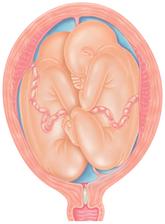

Jak asi víte, těhotenství je členěné na tři časové úseky, kterým říkáme trimestry – každý z nich trvá tři měsíce. Každý z trimestrů je zcela specifický, probíhají v něm určité charakteristické změny, podstupuje se vyšetření a nesou s sebou jiné pocity a obavy nastávající maminky.

- I. trimestr = 1. - 12. týden těhotenství

- II. trimestr = 13. - 28. týden těhotenství

- III. trimestr = 29. - 40. týden těhotenství